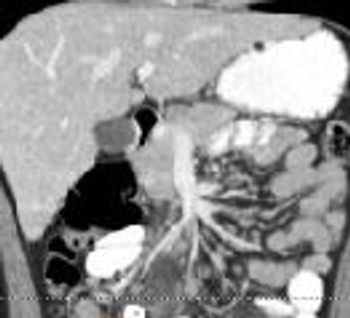

This 42-year-old woman lost 100 lb during the year after gastric bypass surgery. Now, she is diagnosed as having an ulcer. What might be the cause of the lesion?

Some 30% of cases of acute appendicitis in children are associated with appendicolith.